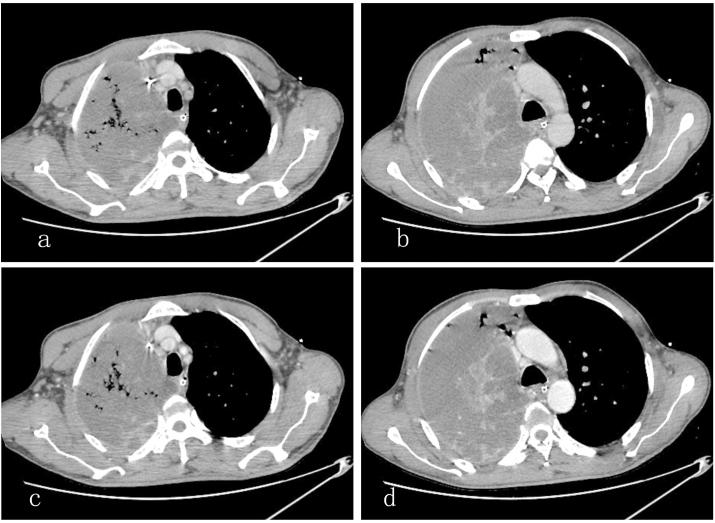

Hypervirulent (hvKP) can cause lung abscess, serious infection, and has a high mortality. Drainage plays a key role in the treatment of lung abscess secondary to hvKP. Contrast-enhanced ultrasound (CEUS) can identify necrotic areas within peripheral pulmonary lesions. We report a case in which thoracic CEUS using solution of sulfur hexafluoride microbubbles (SonoVue®, Bracco, Milan, Italy) was better than computed tomography (CT) in depicting lung abscess from consolidation secondary to hvKP, and its role in guiding drainage of lung abscess. CEUS is a promising imaging technique for confirming an appropriate time for drainage of lung abscess secondary to hvKP, for point-of-care application in critical patients with impaired renal function which may be aggravated by CT contrast medium.

高毒力肺炎克雷伯菌(hvKP)可导致肺脓肿、严重感染,且死亡率高。引流在hvKP所致肺脓肿的治疗中起关键作用。对比增强超声(CEUS)可识别周围肺部病变内的坏死区域。我们报告了1例使用六氟化硫微泡溶液(声诺维®,意大利米兰百胜公司)进行胸部CEUS在描绘hvKP所致实变引起的肺脓肿方面优于计算机断层扫描(CT)的病例,及其在指导肺脓肿引流中的作用。CEUS是一种很有前景的成像技术,可用于确定hvKP所致肺脓肿的合适引流时间,适用于肾功能受损的重症患者床旁应用,这类患者可能因CT造影剂而使肾功能恶化。